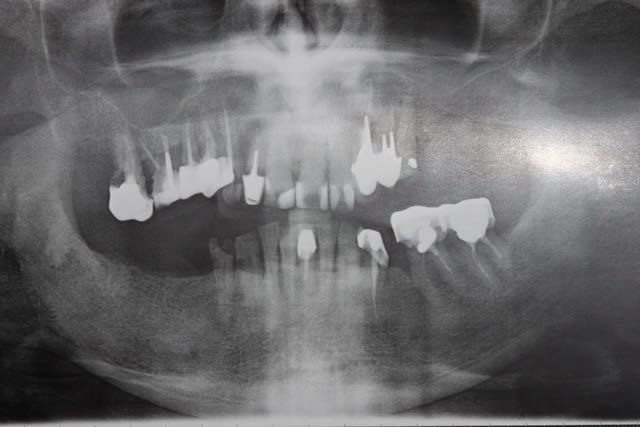

Allez, cas fini cette semaine, je vous le présente tel qu'il est arrivé.

La pano est dégueulasse, à l'époque je n'avais pas encore la mienne, merci les radiologues.

Pour compléter donc:

-pas de lésions apicales visibles, les dents non dévitalisées répondent au test de vitalité.

-Pas de poches supérieures à 6 mm.

-La 23 est foutue, cariée jusqu'au trognon.